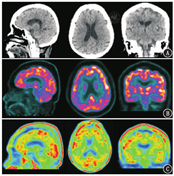

患者女,73岁,受教育程度:6年(小学文化)。因"出现幻视半年余伴认知障碍(主诉看到已过世或不存在的人及经常不能认出丈夫)、进行性记忆下降3年余"就诊。体格检查:血压130/80 mmHg(1 mmHg=0.133 kPa),双侧瞳孔等大正圆,反应迟钝,双侧鼻唇沟等深,四肢肌张力增高,双上肢和双下肢腱反射未引出,无颈项强直,Kernig征阴性。神经精神心理学评估:计算力明显下降,不能配合完成神经精神量表检查。既往史:高血压10余年,控制可,无糖尿病、症状性脑卒中等病史。实验室检查:甲状腺功能正常,叶酸、血清维生素B12正常,梅毒筛查甲苯胺红不加热血清试验(toluidine red unheated serum test, TRUST)阴性。头颅MRI示:T1加权成像(weighted imaging, WI)未见明显异常(图1A);T2WI示多发非对称性白质高信号病灶并延伸至皮质下白质(图1B);弥散WI(diffusion WI, DWI)未见明显异常(图1C);磁敏感WI(susceptibility WI, SWI)示颅内散在皮质、皮质下多发微出血病灶(图1D)。18F-脱氧葡萄糖(fluorodeoxyglucose, FDG)及淀粉样蛋白显像剂18F-florbetapir[AV-45;AV-45显像得到本院伦理委员会的批准(批准号:2018-191),患者签署知情同意书]由本院核医学科自制,PET/CT(德国Siemens Biography mCT)显像结果如下:CT示右侧脑室旁腔隙性脑梗死灶(图2A);双侧顶叶、双侧枕叶和右侧额叶弥漫性FDG代谢轻度减低(图2B);双侧额叶、颞叶、顶叶和枕叶皮质见淀粉样蛋白沉积(图2C)。根据脑淀粉样血管病(cerebral amyloid angiopathy, CAA)波士顿诊断标准[1,2],最终临床诊断为CAA。

本例患者年龄73岁,缓慢起病,临床表现以幻视半年余伴认知障碍为主;其头颅MRI T2WI示多发非对称性白质高信号病灶并延伸至皮质下白质,SWI示颅内散在皮质、皮质下多发微出血病灶,符合影像学诊断标准;患者其他常规检查已排除感染及肿瘤病史,符合CAA波士顿诊断标准全部表现。因为患者认知功能下降,还需要鉴别诊断是否合并AD。首先,未见本例患者有明显海马萎缩,与AD不符;其次,Aβ沉积以双侧枕叶为著,而AD患者较少累及枕叶;最后,本例患者FDG代谢轻度减低而认知功能严重下降,与AD患者认知功能下降幅度和FDG低代谢程度一致的情况不符。因此,最终考虑患者CAA可能性较大,合并AD可能性较小。